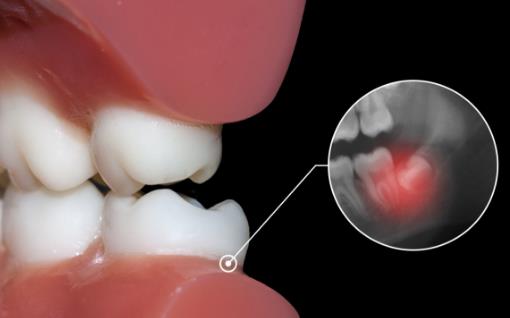

2.侵犯鄰牙:通常患者不自知,而由牙醫以X光診斷得知。通常智齒萌發的空間不足,而會倒在第二大臼齒上,因而造成第二大臼齒清潔不易,甚至是牙齒部分吸收的現象,造成患者不舒適或牙疼。

6.阻生齒:通常這是最討厭的一種,牙醫會覺得很難搞定,但病人卻不一定有感覺,因此忽略了。這一種類型的牙齒,通常埋在齒槽骨的里面,如果會痛,或是診斷會有病灶發生的時候,就需要拔除了。